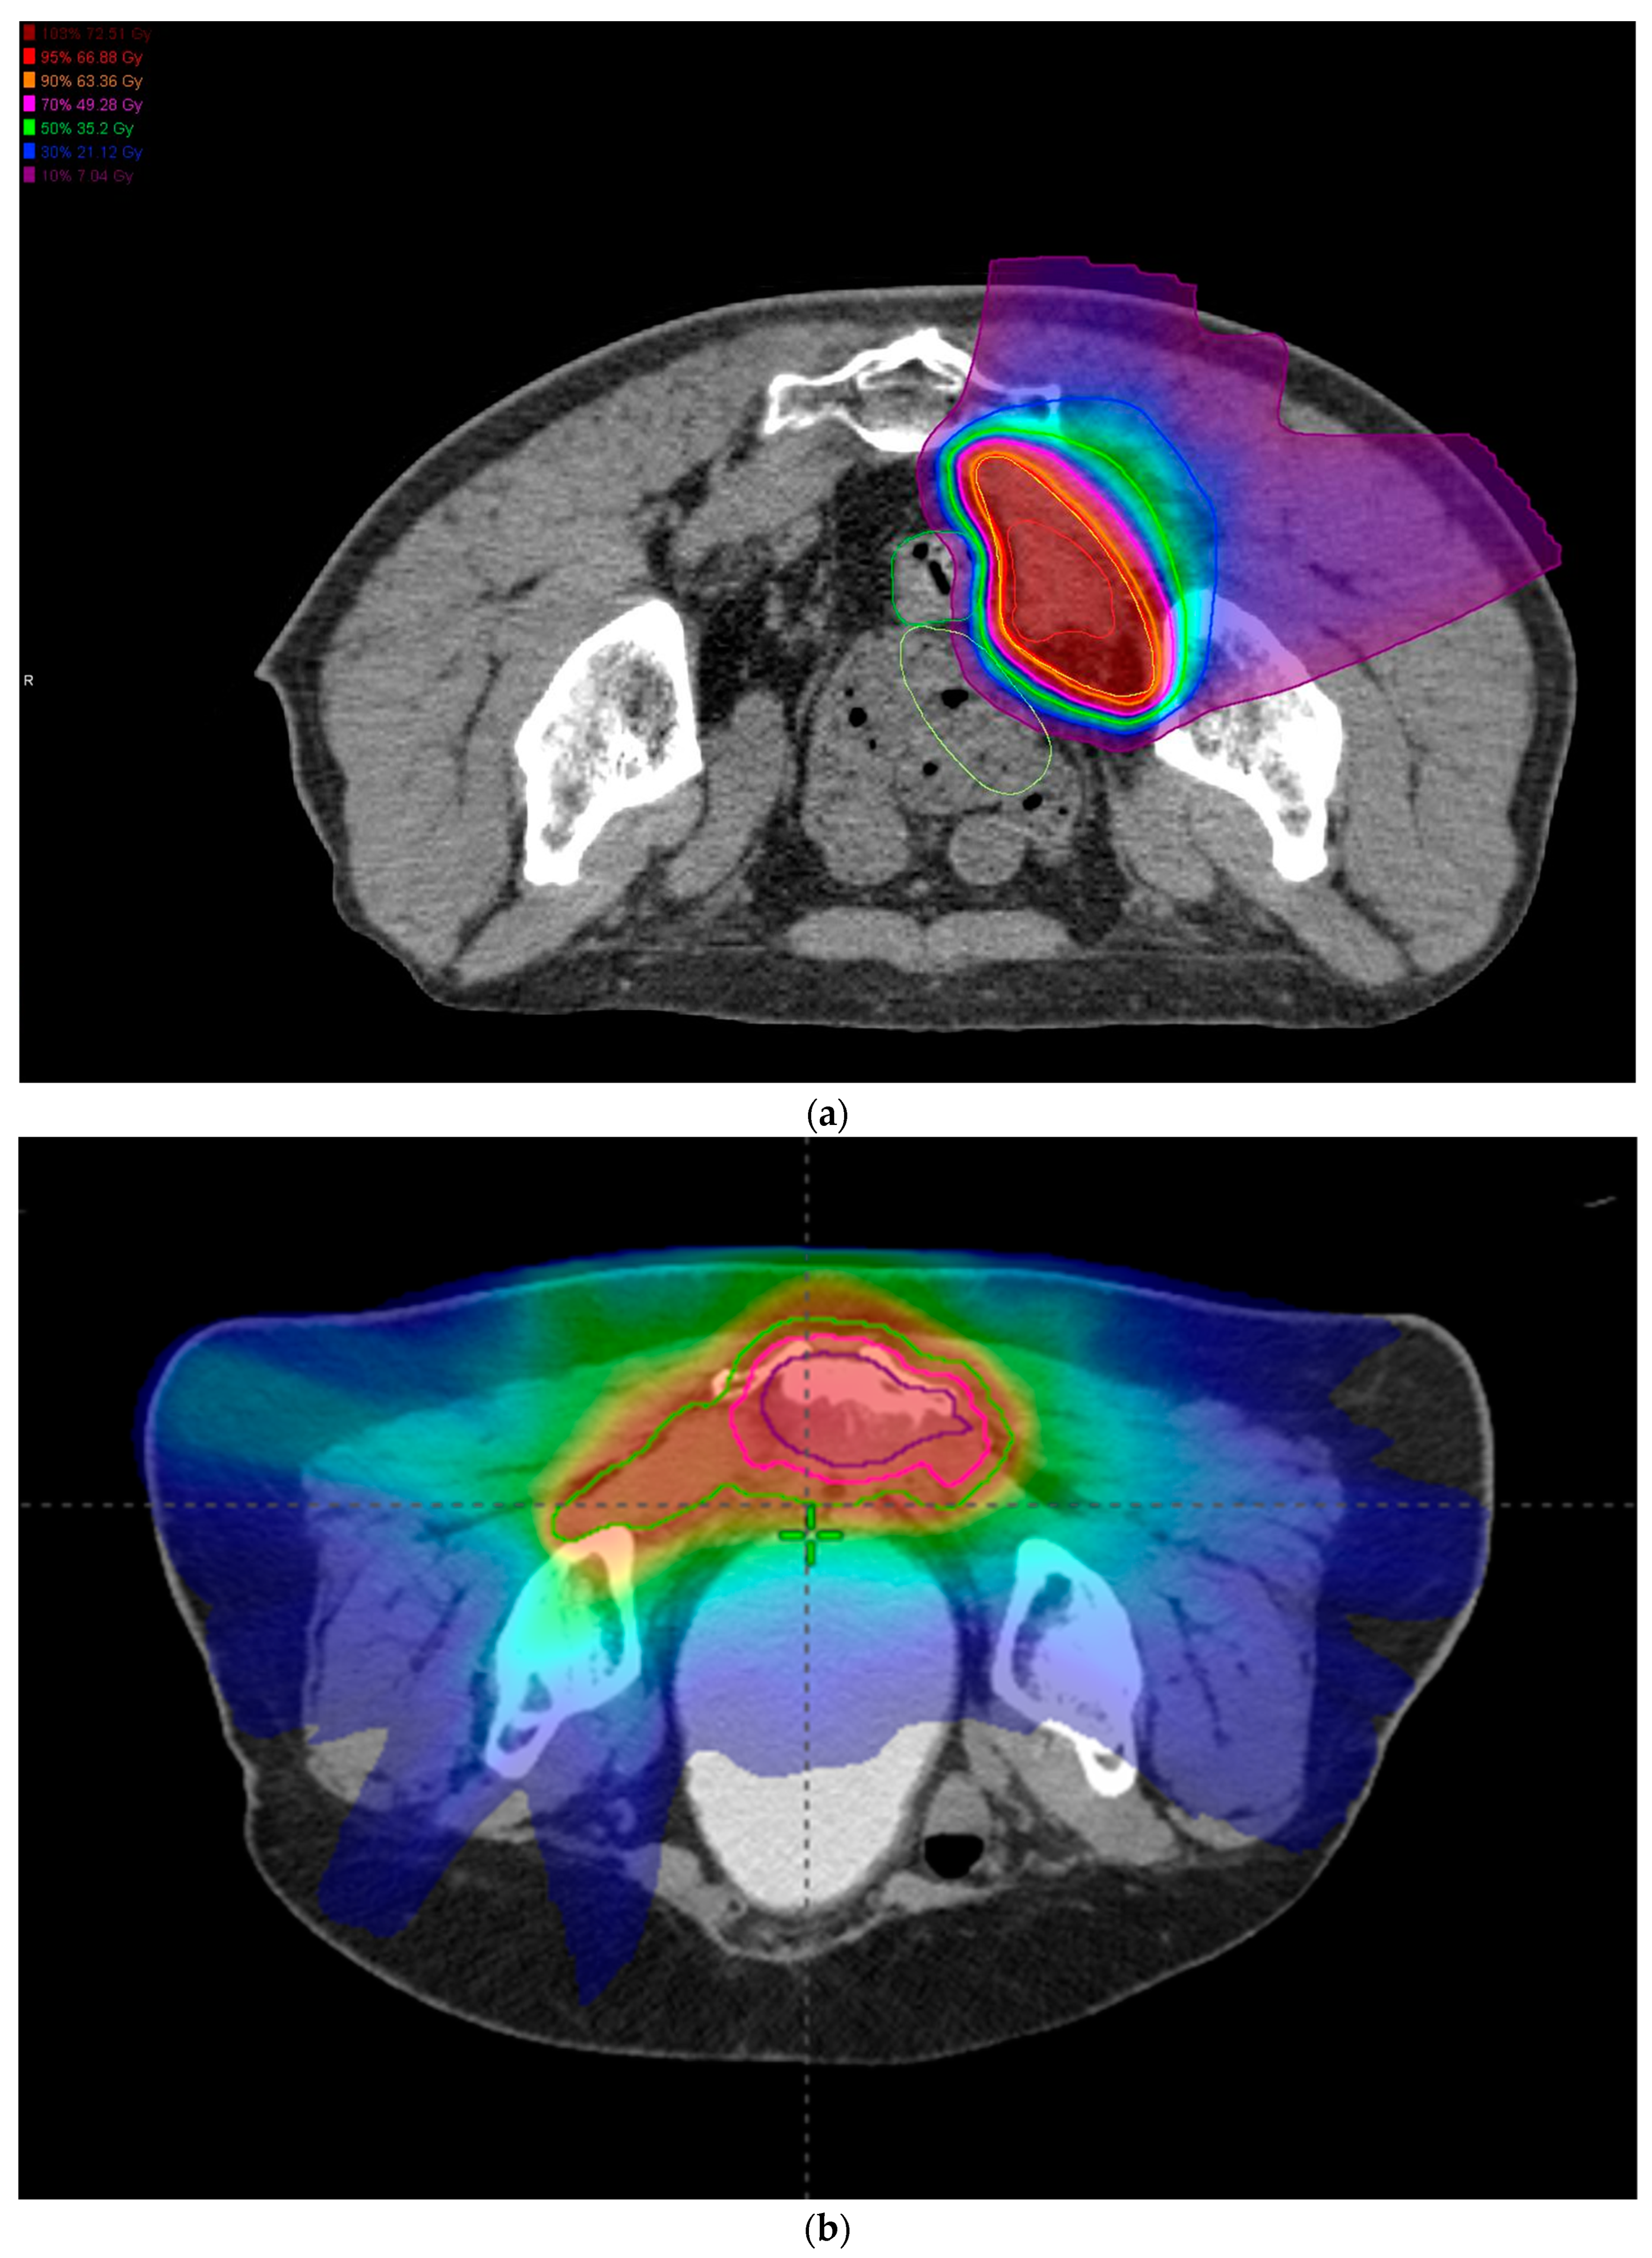

3.1. CMT Patients

3.2. CIRT Patients